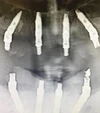

Implant tedavisi